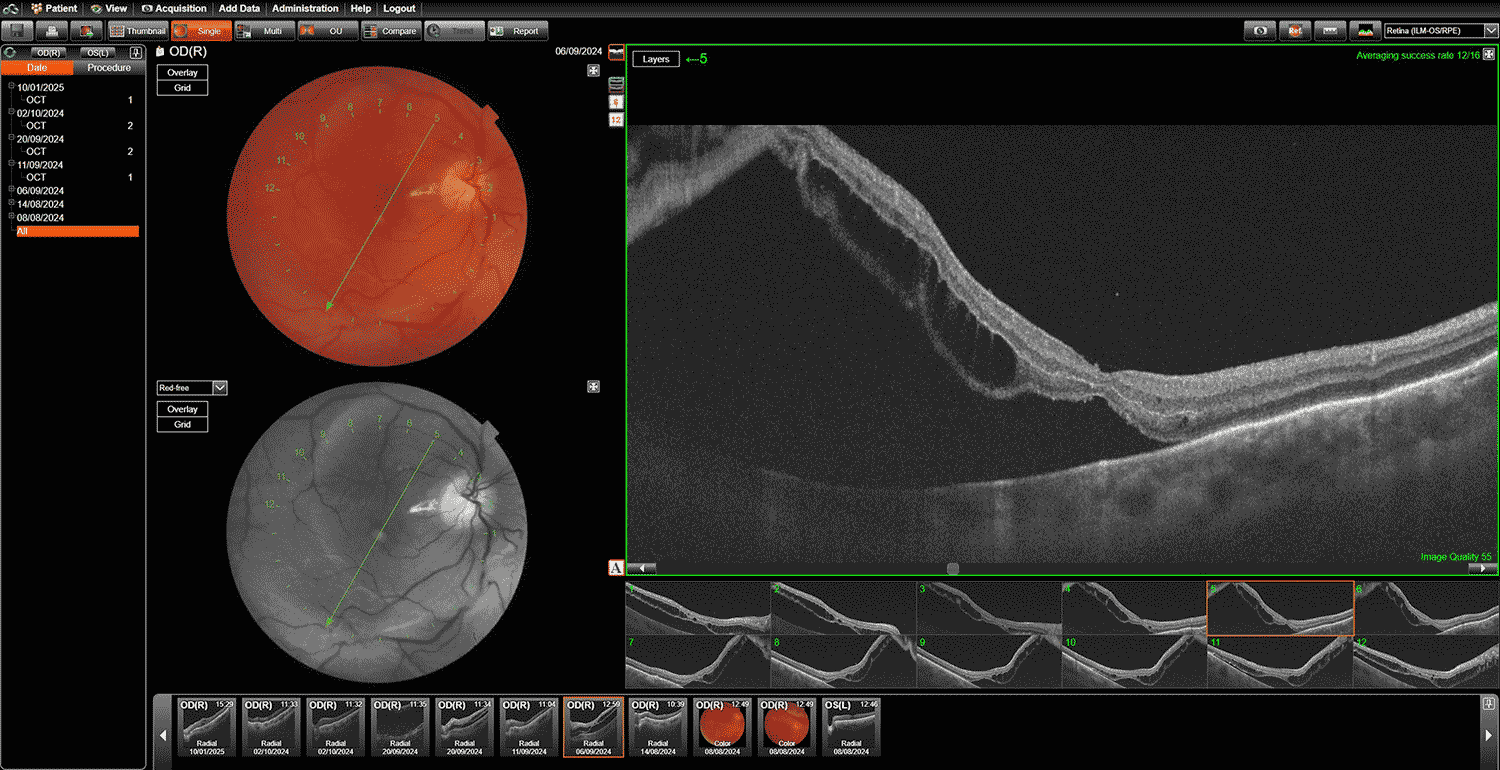

✔ Оптическая когерентная томография (ОКТ) – высокоточное сканирование слоев сетчатки.

✔ Оптическую когерентную томографию (ОКТ) – анализ структуры сетчатки.